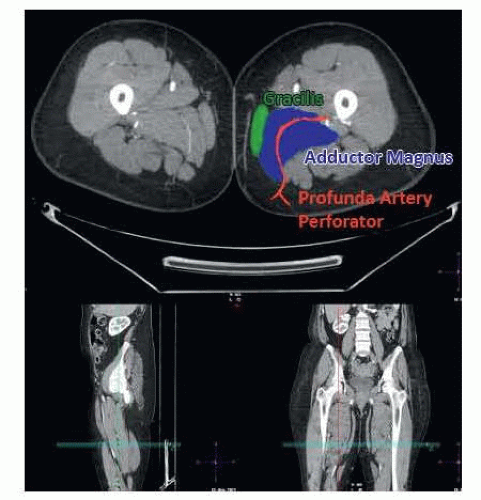

Perforators should be described as they exit the deep muscular fascia and described based on location in an x–y axis. The gluteal fold will be set as zero on the y-axis, and the posterior border of the gracilis will be set as zero on the x-axis (FIG 3).

FIG 3 • CTA of the lower extremity identifying the location of the profunda artery perforator behind the gracilis traversing the adductor magnus toward the profunda femoris artery.

The description of the perforator should include the size of perforator as it exits the fascia, length of course to the profunda femoris, distance from midline, and distance from gluteal crease. Additional information includes location of the perforator in relation to gracilis, adductor longus, adductor magnus, and semimembranosus.